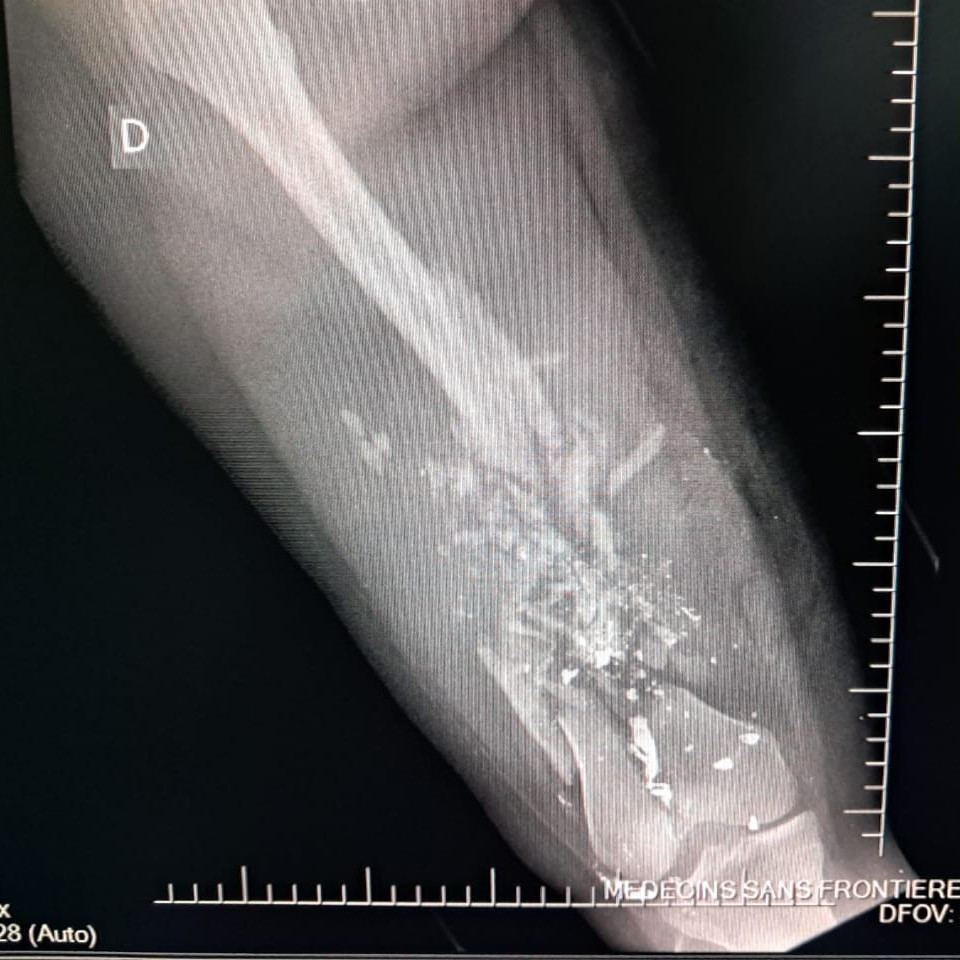

En los primeros seis meses de 2025, los equipos de MSF atendieron a 2.600 supervivientes de violencia sexual, ingresaron a 13.300 pacientes en urgencias y trataron a 2.267 víctimas de violencia. De estas últimas, el 26 % eran menores de edad, frente al 11 % en 2024. La mayoría de los menores tenían menos de 15 años y un tercio eran niñas. En este periodo, uno de cada tres menores ingresados por lesiones relacionadas con la violencia sufría heridas de bala.

El 20 de septiembre, 17 heridos fueron atendidos en el hospital de MSF en Drouillard tras un ataque con drones llevado a cabo ese mismo día en el barrio de Cité Soleil. Entre estos pacientes se encontraban dos hombres que ya habían fallecido a su llegada, otro hombre que murió durante el traslado, diez mujeres —una de ellas murió de camino al Hospital de traumatología de MSF en Tabarre— y tres niños que, trágicamente, no sobrevivieron a sus heridas. Otras dos mujeres heridas en el mismo ataque fallecieron en el cercano Hospital materno Isaïe Jeanty, donde también trabaja MSF.

Esta situación también ejerce una presión extrema sobre los centros que siguen funcionando, en particular el Hospital de traumatología de MSF en Tabarre, que ha aumentado su capacidad en un 50 %, con uno de cada cuatro traumatismos relacionados con la violencia. Solo un gran hospital público sigue funcionando en la capital, el Hospital Universitario La Paz, centro que se ve desbordado con frecuencia.